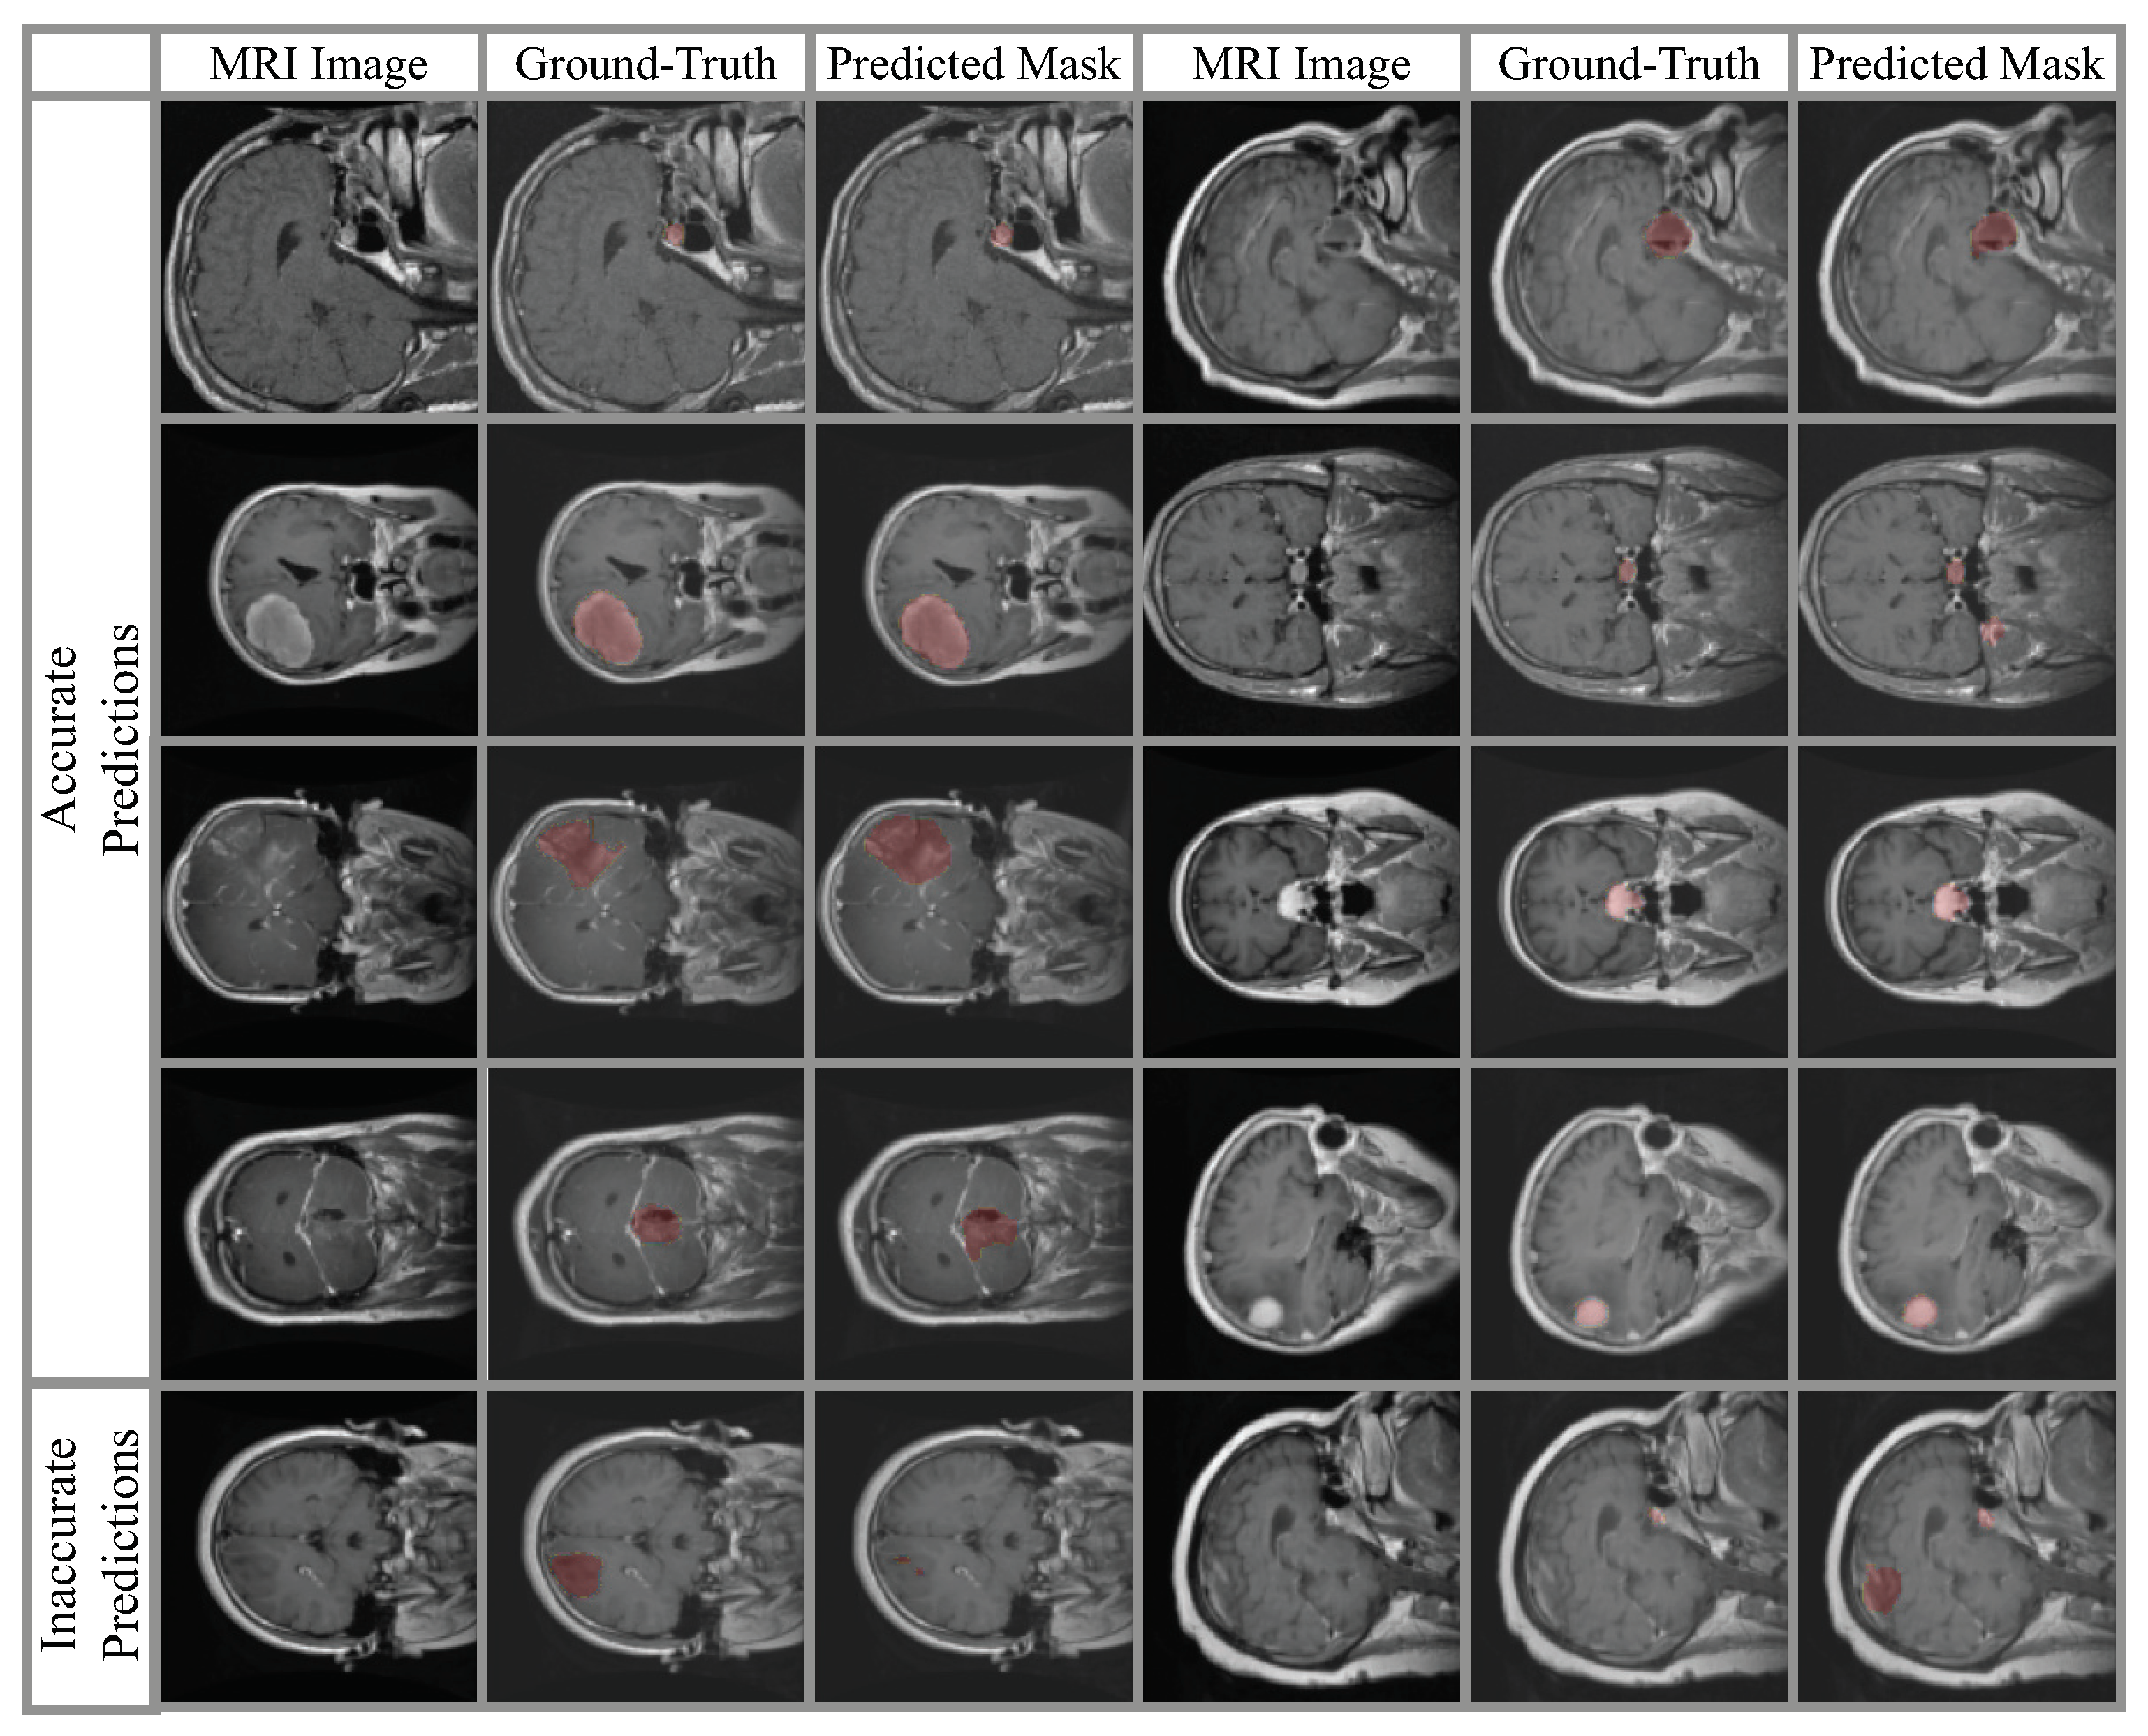

4.2. Classification Results